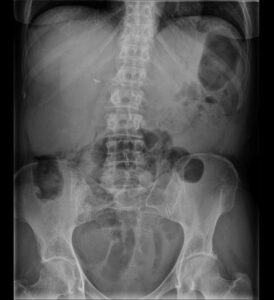

Caso 11

(Rx simple de abdomen)